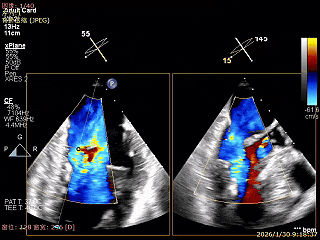

术前超声评估

经胸超声报告提示:患者二尖瓣2区及3区前叶关闭时脱入左房,二尖瓣重度反流(MR 4+),患者LA前后径约52mm,LVEDD约68mm,LVESD约42mm,EF值:65%,经胸超声测二尖瓣瓣口面积约6.1cm2,主动脉瓣无冠瓣脱垂并中重度反流,三尖瓣中度反流,估测中度肺动脉高压。

经食道超声精细化测量:肺静脉逆流,房间隔可穿刺高度约4.2cm,Flail宽度约21mm,Flail高度约8mm,Flail Gap约4mm, 3区AML长约23mm、PML长约12mm、2区AML约32.2mm,PML约16mm。

Bicomm切面看2区脱垂

上Color,可见反流主要来自于3区

X-Plane切面切1区未见明显异常

1区上Color,未见反流来源

X-Plane切面切2区可见前叶Flail

2区上Color,可见反流来源

X-Plane切面切3区可见前叶脱垂

3区上Color,可见反流来源

3D Enface 2区及3区前叶脱向左房

3D Enface 可见反流由2区3区从前后冲出

房间隔可穿刺高度约4.2cm

Flail宽度约21mm,Flail高度约8mm

经胸短轴测得瓣口面积约6.1cm2

3区前叶长度约22mm,后叶长度约11.6mm

2区前叶长度约32.2mm,后叶长度约16mm

2区Flail Gap约4mm